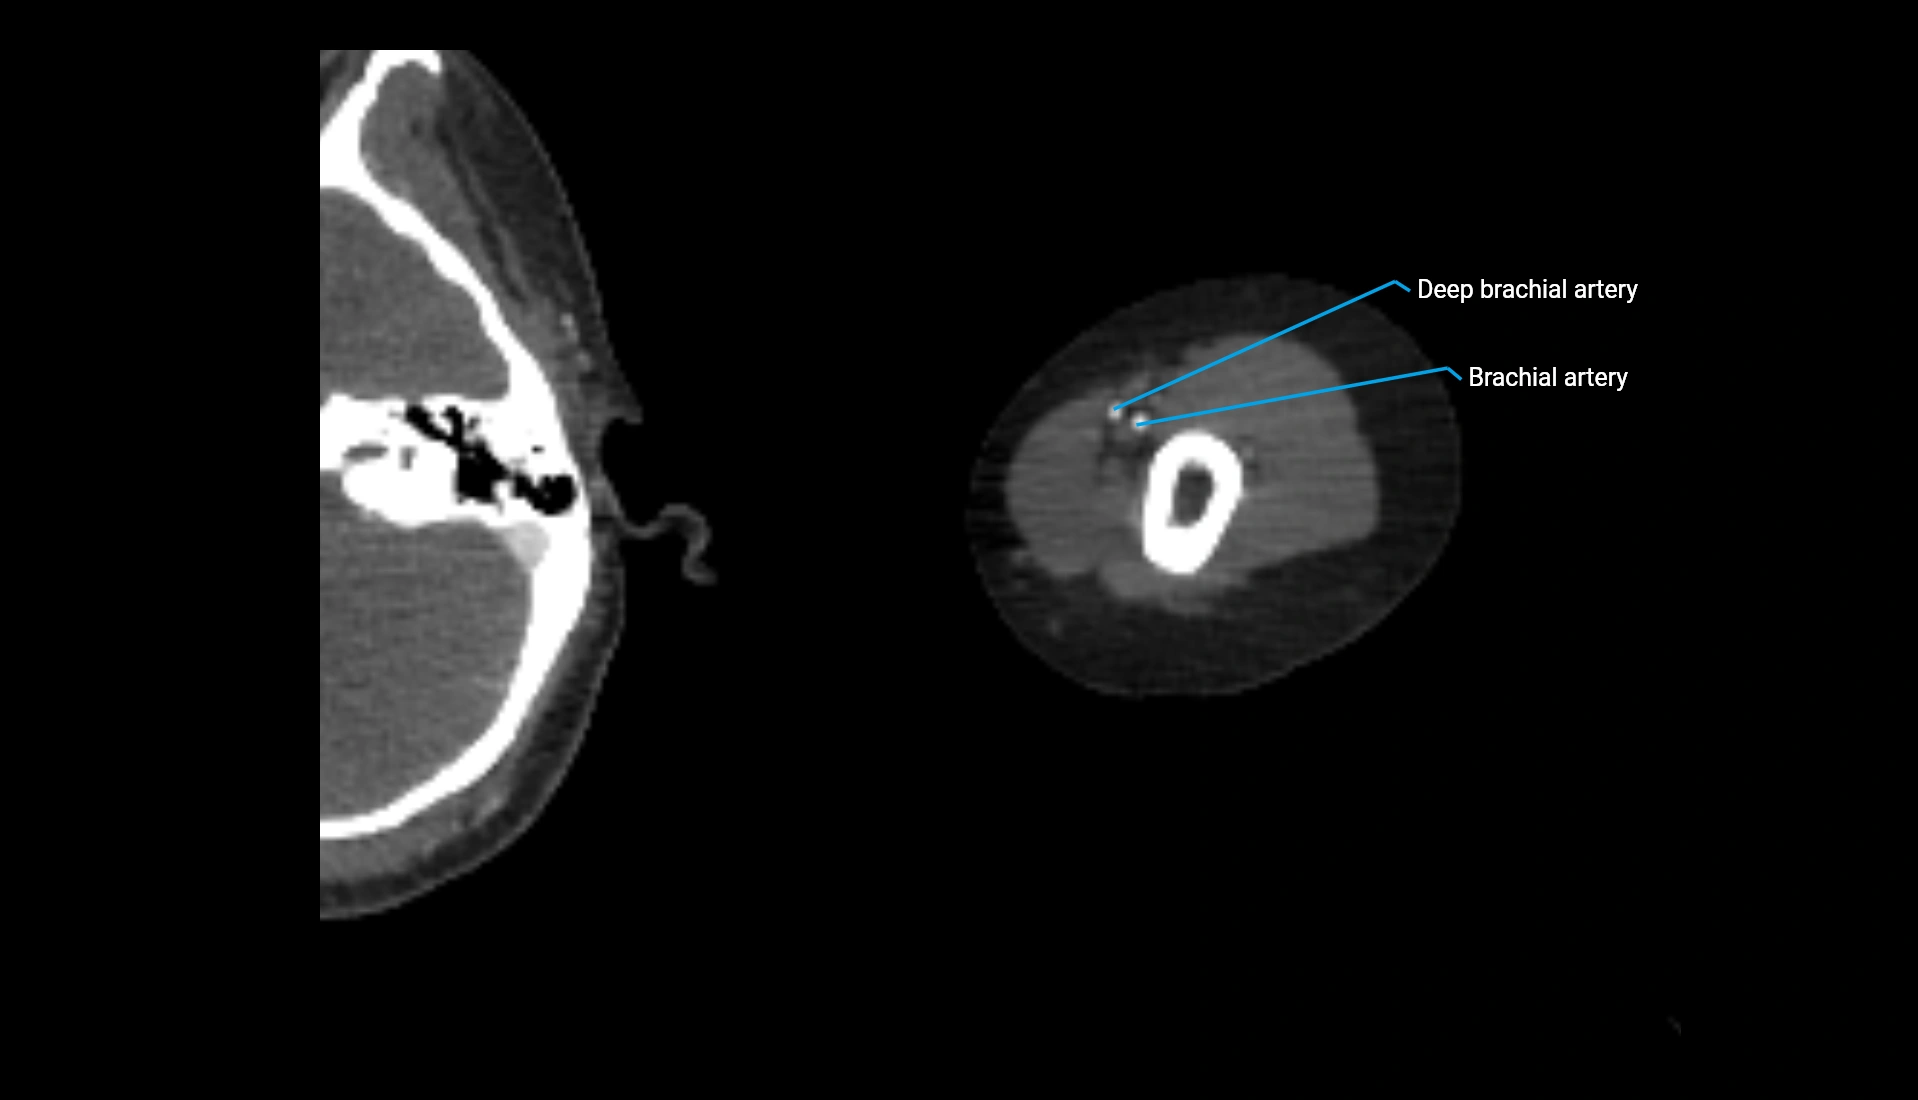

CT Appearance

Non-Contrast CT:

• Cortex: High-density, sharply defined

• Subchondral bone: Dense cancellous matrix

• Articular surface: Smooth concave contour articulating with the capitellum

• Excellent for evaluating bone integrity, alignment, and subtle fractures